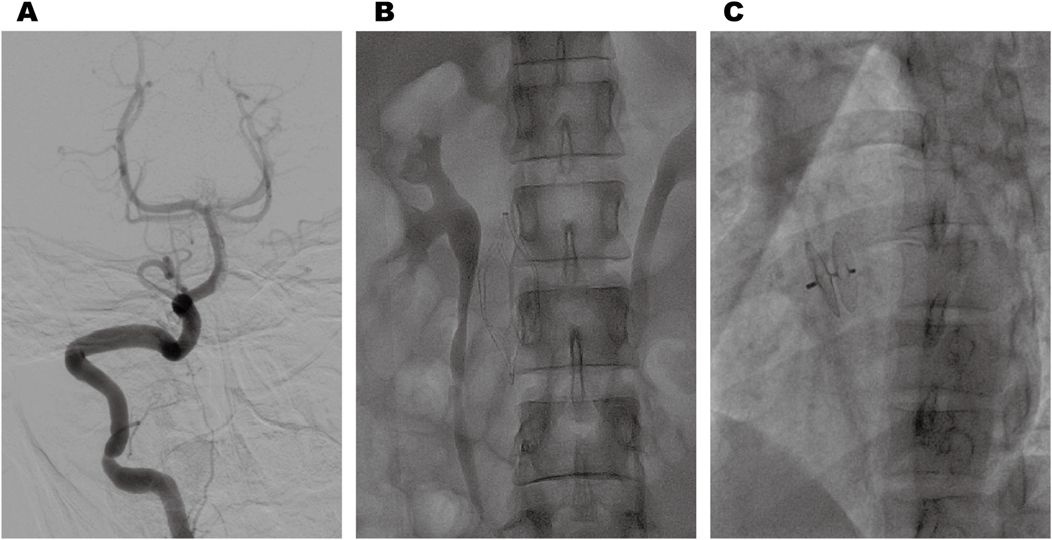

Cranial magnetic resonance imaging (MRI) revealed an acute pontine infarction (Figure 1A). Head and neck computed tomography angiography (CTA) showed basilar artery occlusion (Figure 1B) and incidentally detected left pulmonary artery embolism (Figure 1C), suggesting the possibility of multisystem embolism. Further digital subtraction angiography (DSA) of the whole brain confirmed interruption of blood flow in the distal basilar artery (Figure 2A). Pulmonary angiography revealed left pulmonary artery embolism (Figure 2B). Antegrade venography of the lower extremity deep veins showed bilateral iliac vein thrombosis (Figures 2C,D). The patient underwent emergency mechanical thrombectomy of the basilar artery and placement of an inferior vena cava filter (Figure 3B). Post-operatively, imaging evaluation showed the basilar artery was patent (Figure 3A), and the patient was transferred to the neurology department for further treatment.

Figure 1

Cranial MRI revealed an acute pontine infarction (A). Head and neck CTA revealed basilar artery occlusion (B), and incidentally showed left pulmonary artery embolism (C).

Figure 3

Post-thrombectomy imaging revealed normal anterograde blood flow in the basilar artery (A). Postoperative changes following inferior vena cava filter implantation (B). Post-procedural imaging revealed appropriate positioning of the PFO closure device (C).